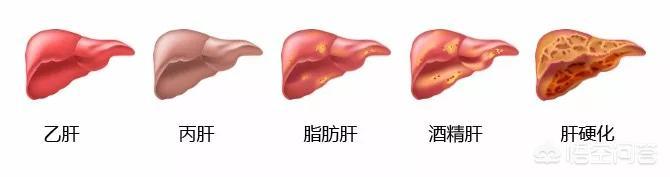

转氨酶偏高,通常与乙肝、丙肝、脂肪肝、酒精肝和肝硬化等疾病有关,具体是何种原因引起,需通过检查确定。